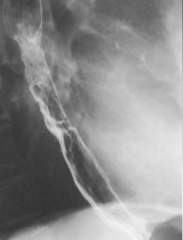

Image TOGD une hernie

hiatale de type III . Estomac en ce cas en roulement

dans le thorax et le cardia glisse au dessus

diapragmatique |

Meme cas

en coupe TDM sagitale |